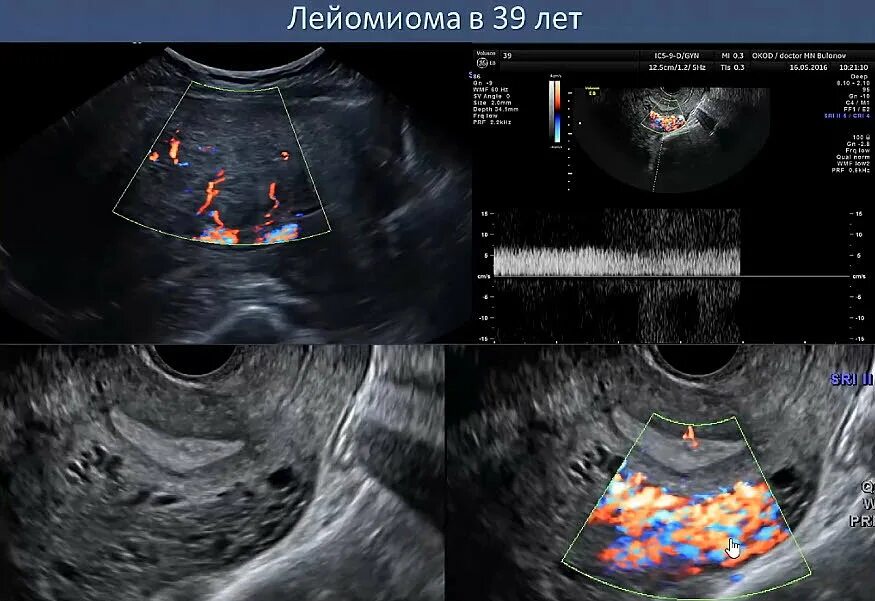

Тромб в матке